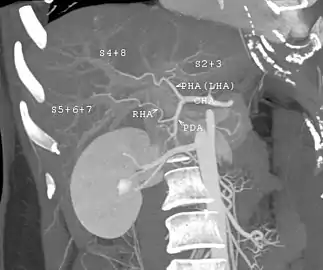

CT scan performed for evaluation of a potential donor. The image shows an unusual variation of hepatic artery. The left hepatic artery supplies not only left lobe but also segment 8. The anatomy makes right lobe donation impossible. Even used as left lobe or lateral segment donation, it would be very technically challenging in anastomosing the small arteries.